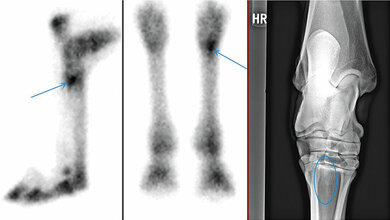

Entscheidende Fortschritte bei der Aufklärung dieser Krankheitsbilder soll die Bewegungsanalyse mit der neuen FluoKin-Anlage bringen, betont die Tierärztin. „Unsere Patienten sollen sich bewegen. Es ist egal, ob sie laufen, kauen oder klettern“, sagt Wagner, die bei der Untersuchung der Tiere trotz der schwachen Röntgenstrahlung einen bleiernen Schutzanzug trägt. Die Anlage besteht hauptsächlich aus zwei Röntgengeräten, die verschiedene Körperregionen der Tiere auf dem Laufband in Bewegung durchleuchten, schräge Strahlengänge ermöglichen und deren Bewegungen dreidimensional darstellen. Wegen der geringen Strahlendosis gebe es dabei kein Zeitlimit. Je nach Größe der tierischen Patienten bewegen sie sich auf einem großen oder kleinen Laufband. Neben den beiden Geräten befinden sich Röntgenbildwandler, die die Strahlung in sichtbares Licht umwandeln. „So entsteht ein Röntgenfilm wie eine Art Schattenkino“, erklärt die Laborleiterin. Dazu kommen vier High-Speed-Kameras, die bis zu 500 Fotos pro Sekunde aufnehmen und dadurch auch sehr schnelle Bewegungen festhalten können.

„Wir können ganz präzise Aussagen treffen, wie sich etwas im Körperinneren bewegt“, beschreibt die Expertin einen Vorteil der neuen Anlage. Bei anderen Bewegungsanalysetechniken seien häufig Verschiebungen der Haut der Tiere ein Problem, die den Blick auf die Knochen erschwerten. Die neue Anlage ermögliche dagegen Aufnahmen mit einer Genauigkeit im Submillimeter-Bereich und sei kombinierbar mit anderen Messtechniken. So können Operationsmethoden optimiert und Bewegungsfehler der Tiere genau analysiert werden. Die Anlage sei auch für Menschen nutzbar, wenn der Bedarf bestehen sollte. Das Bewegungsanalyselabor, das eine andere, veraltete Anlage an gleicher Stelle ablöst, hat 1,2 Millionen Euro gekostet und wurde je zur Hälfte von der Deutschen Forschungsgemeinschaft (DFG) und dem Freistaat Sachsen finanziert. Dieser Antrag wurde gemeinsam mit der AG Biomechanik des Instituts für Allgemeine Bewegungs- und Trainingswissenschaften (Sportwissenschaftliche Fakultät der Universität Leipzig), dem Forschungslabor der Poliklinik für Zahnerhaltung und Parodontologie (Universitätsmedizin Leipzig) und der AG Vergleichende Zoologie des Institutes für Biologie (Humboldt-Universität zu Berlin) eingeworben. Europaweit gibt es nur in Zürich eine weitere vergleichbare Anlage.